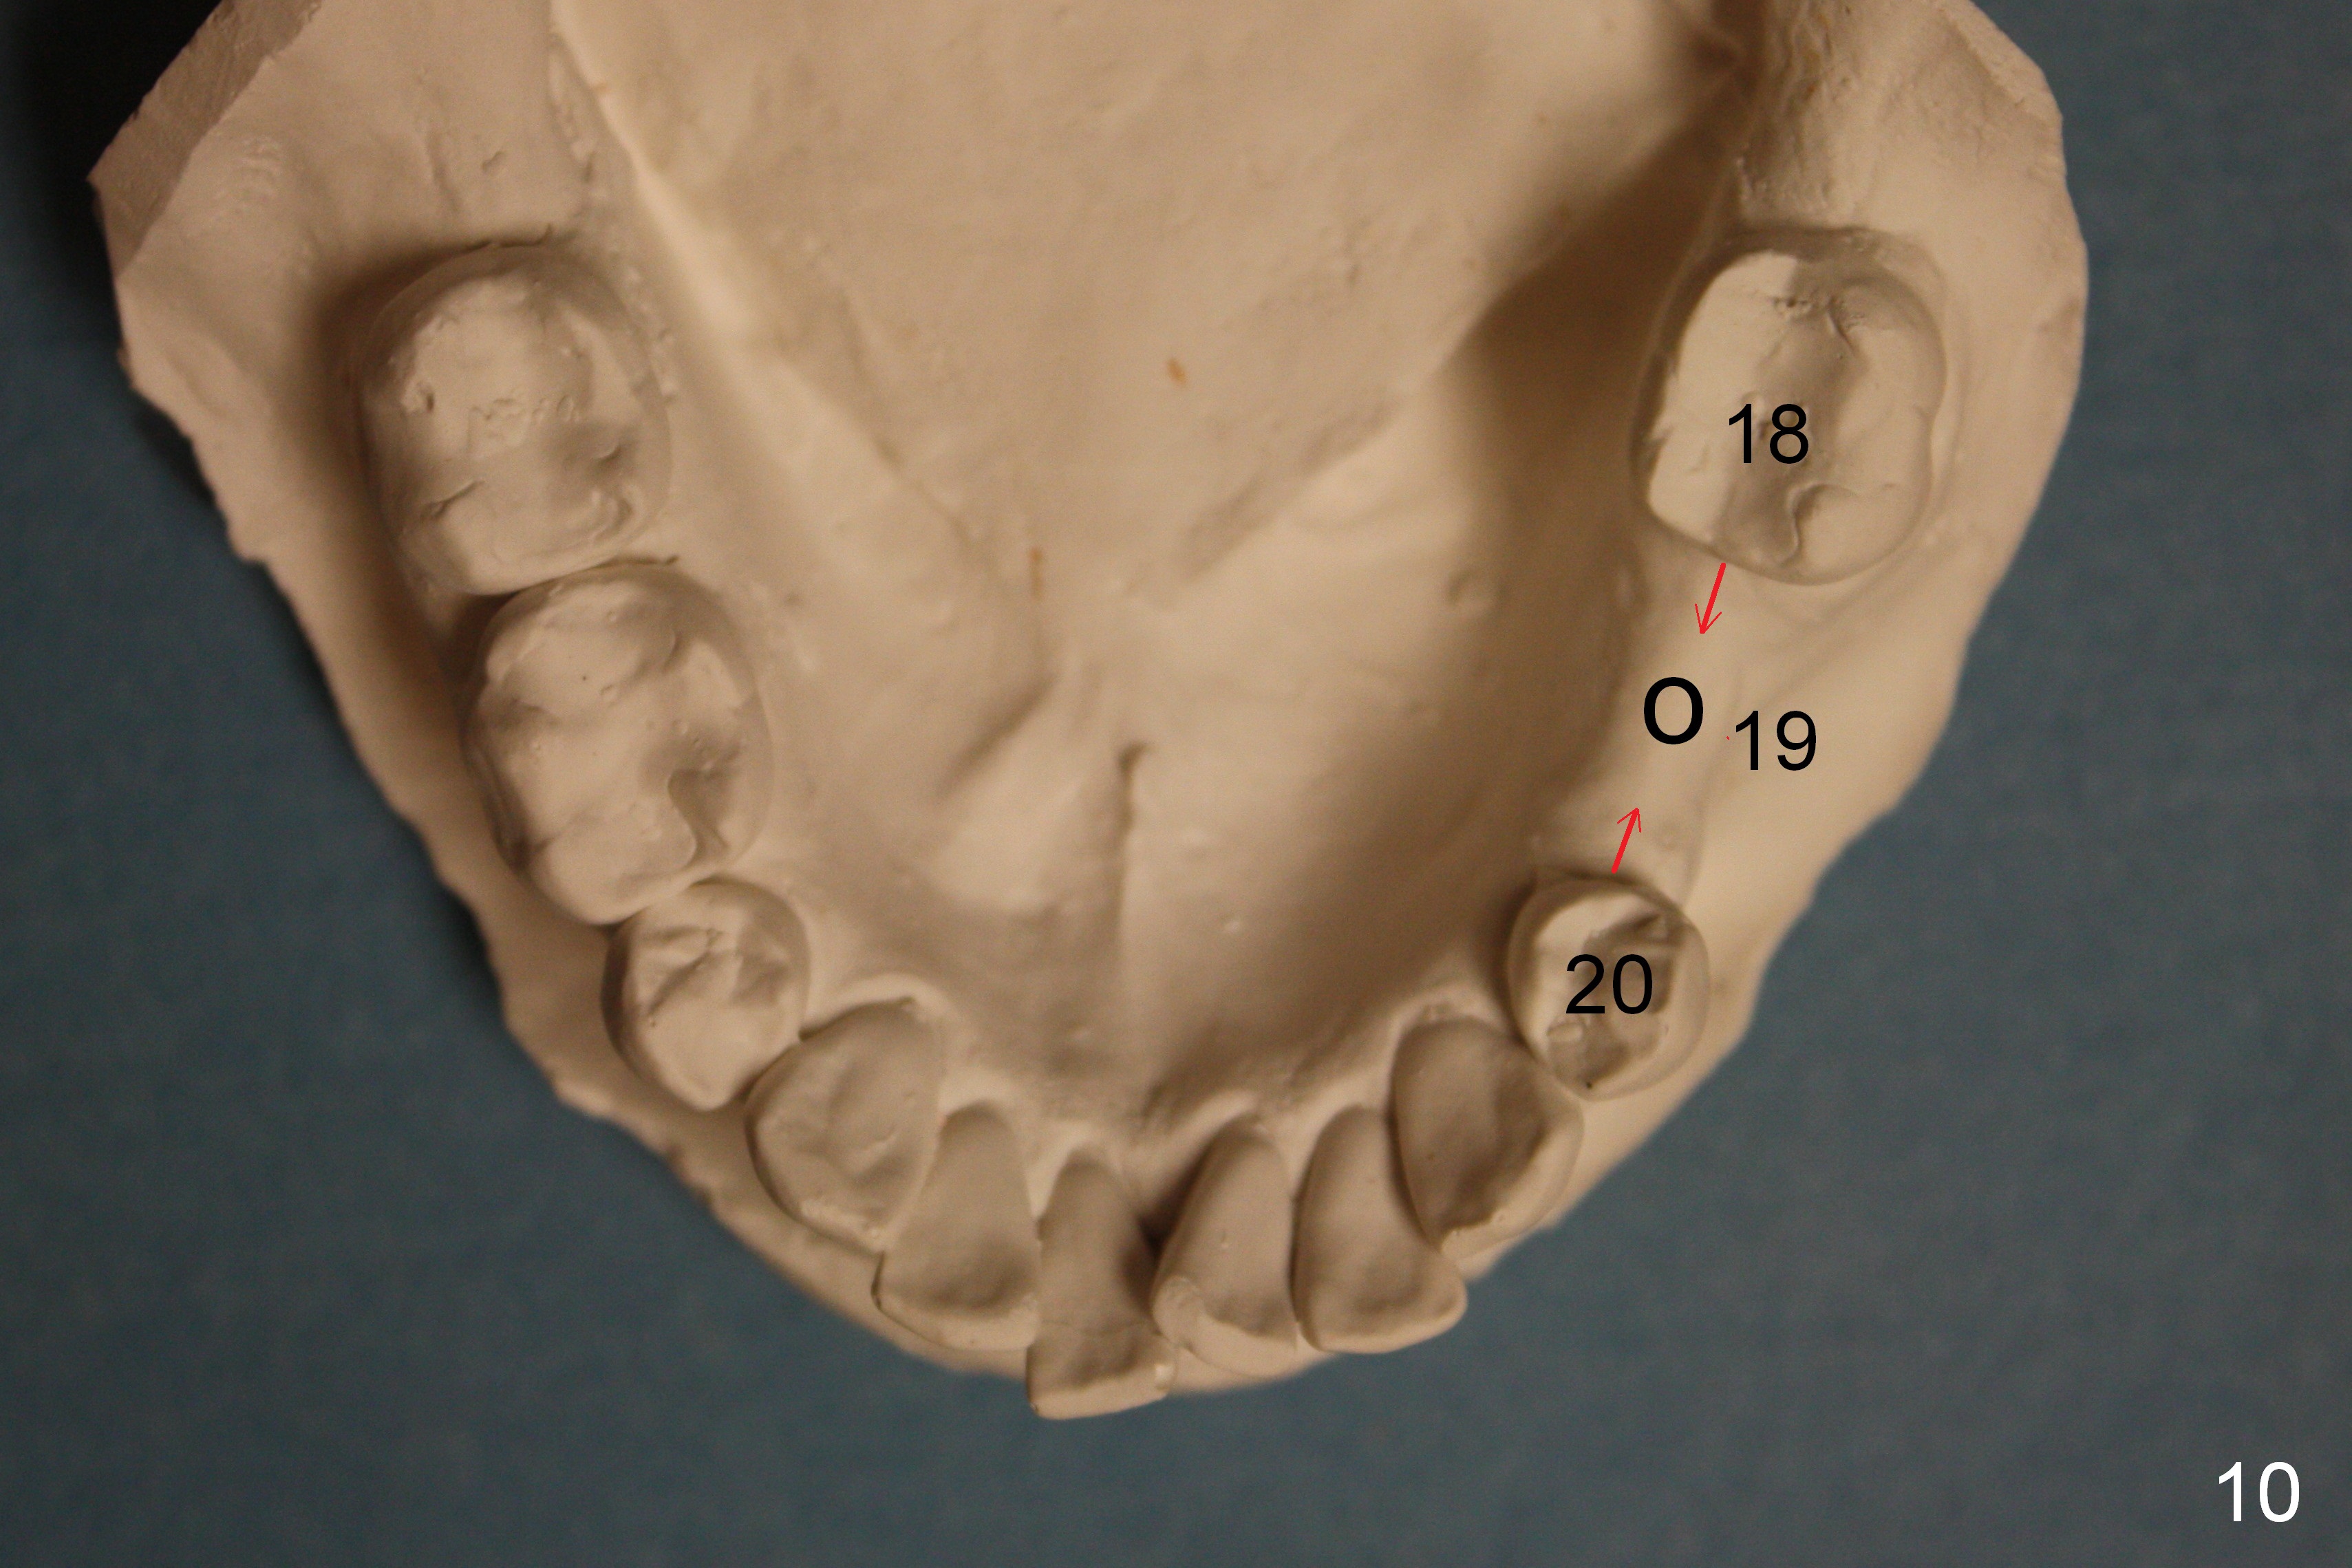

A 44-year-old black lady is a typical dental phobic. She has lost #19 for years with history of traumatic extraction. The ridge is atrophic (Fig.1). She is not comfortable with intraoral X-ray. So CBCT is taken. The coronal section shows that the bone density is low in the coronal ridge (Fig.2 arrowheads). It is difficult to determine the buccolingual width at crest; probably a 5.9x10 mm implant is appropriate (Fig.3). The most useful information from CT is height determination for the implant (Fig.4). The initial osteotomy depth is 10 mm (Fig.5); there is a large safety margin. There is a 2 mm clearance when a 4.5x12 mm implant is placed (Fig.6). Incision is sutured; a 8x4 (3) mm healing abutment is placed (Fig.7 arrowhead), followed by application of perio dressing. The latter remains stable 13 days postop thanks to the holding effect of the healing abutment (Fig.8 H). The wound has apparently healed when the dressing is removed (Fig.9). It appears that the edentulous space is extremely wide. The 4.5 mm implant may not sustain masticatory force. Limited orthodontic treatment appears to be necessary, using the implant as an anchorage to move the neighboring teeth (Fig.10 arrows). In fact the orthodontic treatment is not rendered. A crown is cemented 14 months postop. The cortical bone is thickened around the implant 15 months post cementation (Fig.11).